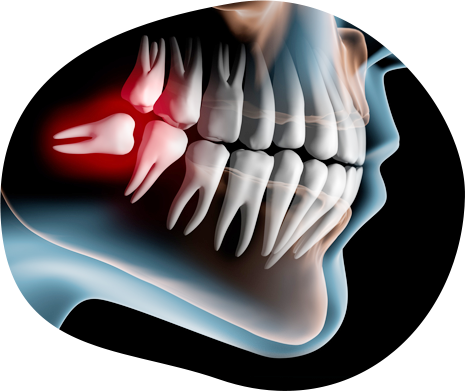

歯科口腔外科では、お口の中のできもの、顎や親知らずの痛みなど、むし歯や歯周病以外にも幅広く治療を行います。

お口の症状は、口内炎などの軽い症状がほとんどだからという理由で軽視されてしまうことがありますが、稀に口内炎だと思っているものが口腔がんだったというような例もあります。

お口の中の症状や気になることがございましたら、些細なことでもぜひご相談下さい。

- 親知らずが痛い

むし歯や歯周病以外のお口のトラブルに対応する歯科口腔外科では外科的治療を行うため、担当医の知識や技術がとても大切です。

当院では、歯科口腔外科での治療に専門医を招きますので、

一般的な歯科医院で受ける口腔外科治療よりも専門性の高い治療が受けられます。